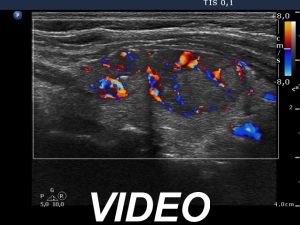

Ultrasonography. The thyroid was echonormal. There was a hypoechoic lesion in the upper while a heterogeneous, dominantly hypoechoic nodule in the lower part of the right lobe. The nodule margins were a bit undulated.

Cytology of the larger, heterogeneous nodule resulted in Hashimoto's thyroiditis.